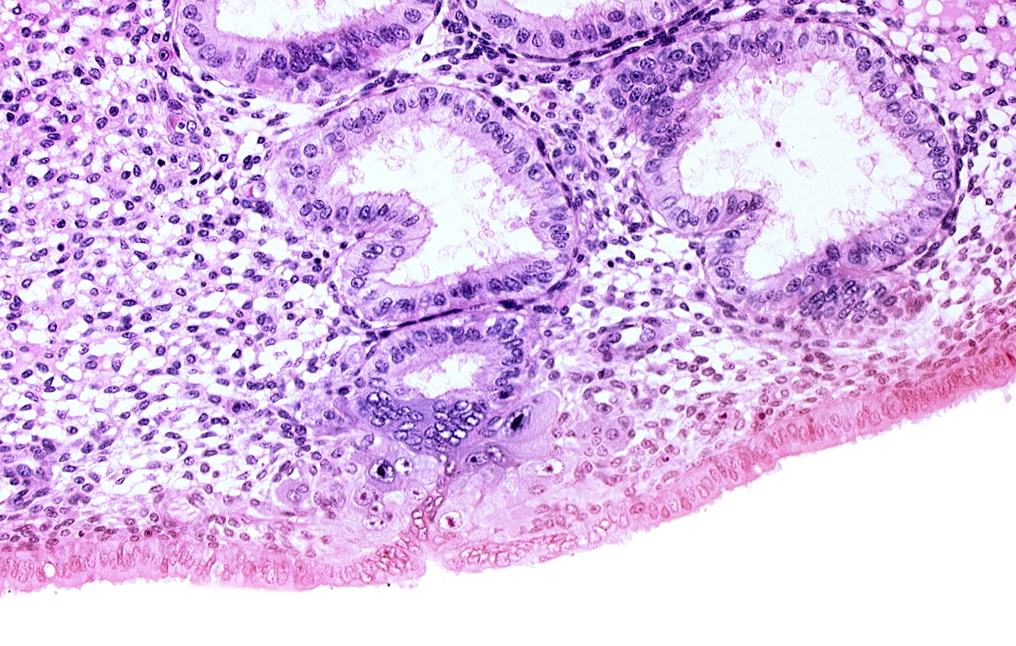

Carnegie Embryo #8020 | Location: 05-04-09

Keywords: cytotrophoblast, endometrial epithelium, endometrial gland, endometrial sinusoid, solid syncytiotrophoblast, uterine cavity